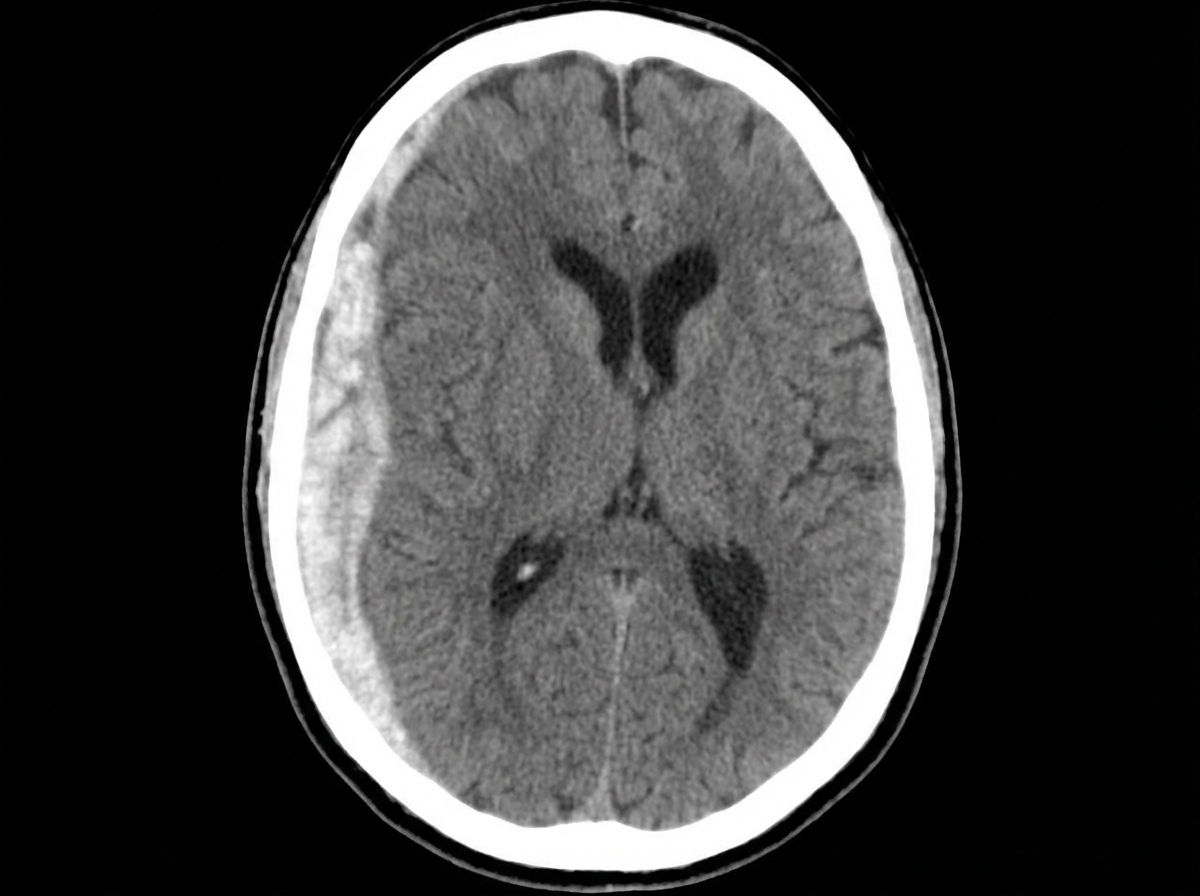

Following a sudden impact in an accident, a 34-year-old race car driver becomes unconscious and is admitted to the hospital. A CT scan reveals a right space-occupying lesion. What is the most likely diagnosis?

Explanation: ***Acute subdural hematoma*** - **High-speed trauma** with immediate **loss of consciousness** is classic for acute subdural hematoma, which results from **bridging vein tears** between cortex and dura. - CT shows **crescent-shaped hyperdense collection** that **crosses suture lines** with potential **midline shift**, consistent with a space-occupying lesion. *Corpus callosum injury* - Typically occurs in **diffuse axonal injury** and would not present as a **space-occupying lesion** on CT scan. - Usually associated with **small hemorrhagic lesions** in corpus callosum, brainstem, and white matter, not a large hematoma. *Acute epidural hematoma* - Presents with **biconvex (lens-shaped)** hyperdense collection that **does not cross suture lines** on CT scan. - Often associated with **temporal bone fracture** and **middle meningeal artery** injury, with classic **lucid interval** before deterioration. *Pituitary apoplexy* - Involves **spontaneous hemorrhage** into the **pituitary gland**, not related to trauma mechanism described. - Presents with **severe headache**, **visual field defects**, and **hormonal dysfunction**, not immediate unconsciousness from impact.